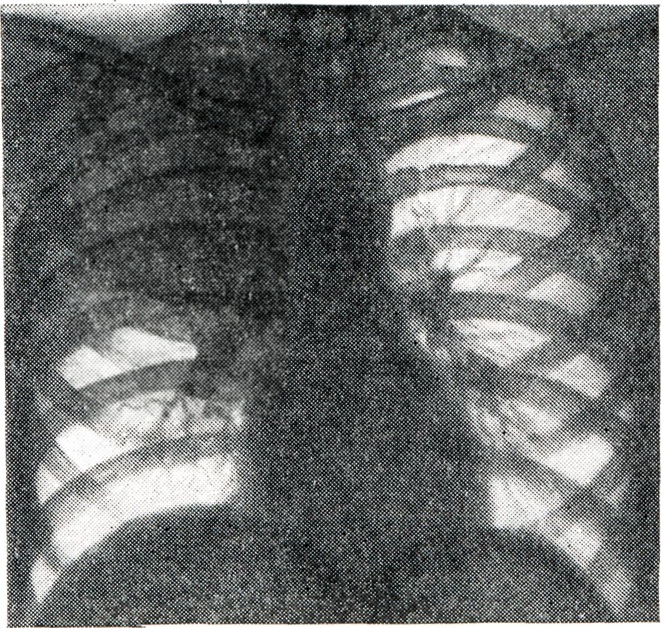

ПрофилактикаДля профилактики дистензионного ателектаза у лежачих больных необходимо раннее применение лечебной физкультуры, устранение факторов, ограничивающих диафрагмальное дыхание (ликвидация метеоризма применением диеты, назначение очистительных клизм и слабительных средств при задержке стула; назначение анальгетиков при болях, связанных с дыханием). Ателектаз у детейАтелектаз у детей наиболее часто локализуется в нижней и средней долях правого легкого (рис. 6), однако может развиться и в других отделах, в частности в верхних долях обоих легких, особенно при пневмонии и бронхиальной астме. Сравнительная узость трахео-бронхиального дерева и склонность к гиперергическим реакциям со стороны слизистой оболочки трахеи и бронхов у детей создают благоприятные условия для развития А. К возникновению ателектаза у детей ведет попадание инородных тел в трахео-бронхиальное дерево, различные формы острой пневмонии, бронхоспазм при бронхиальной астме. Ателектаз легкого у детей может развиваться постепенно. Врачебная тактика при ателектазе у детей должна быть особенно активной, так как морфологические изменения в ателектазированных отделах легкого у ребенка развиваются быстрее, чем у взрослых. Ателектаз оперированного легкого является частым осложнением операции на легких у детей (рис. 7). С целью профилактики послеоперационных ателектазов проводятся следующие мероприятия: обучение ребенка правильному дыханию до операции, полноценная санация трахео-бронхиального дерева до и во время операции, укладывание ребенка на здоровый бок, применение эффективного обезболивания, комплекса лечебных упражнений, а при необходимости ми-ротрахеостомии (смотри Трахеостомия) и аппарата «искусственный кашель» в послеоперационном периоде. Хорошему расправлению легкого способствует отсасывание с помощью катетера содержимого из бронхов в первые сутки после операции. При отсутствии эффекта показана лечебная бронхоскопия.